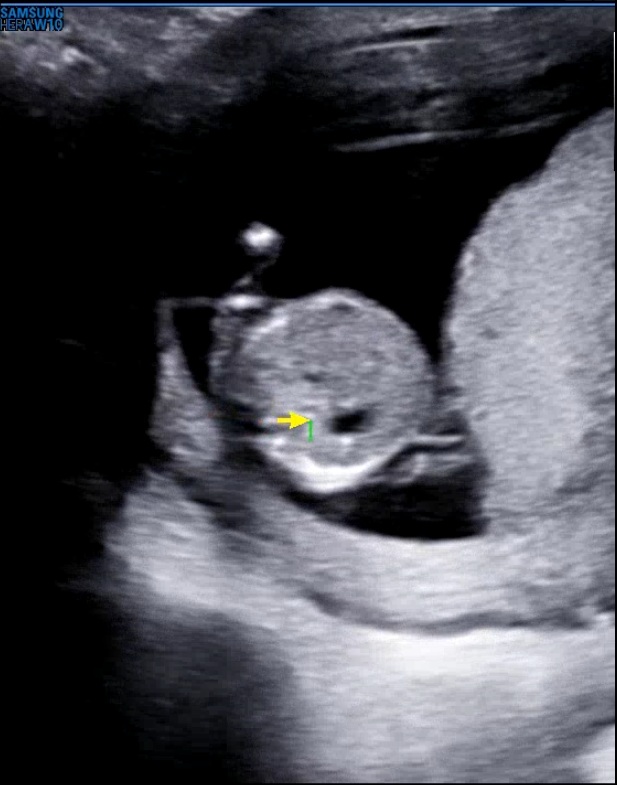

그럼 12주차 우리 아기의 모습을 보자

크기는 7cm 정도인데 팔다리랑 생길건 다 생겨서 엄청 꼬물꼬물 귀엽다 ㅎㅎ

저게 실시간으로 보고있는거라 팔이 움직이는게 보이니까 너무 귀여웠다. 코도 있고 잘보면 발가락 같은것도 보이는데 엄청 조그마해서 심쿵...

아직은 얼굴윤곽이 잘 나오진 않지만 아마 크면 금방 볼 수 있을 것 같다 ㅎㅎ

일단 심장부터 확인했고, 분당 150회 정도로 잘 뛰고 있었다. 이전에는 분당 180회였는데 아무래도 커가면서 조금씩 심장속도가 다시 느려지는 것 같다.

목둘레 투명대도 쟀는데 정상이였다. 정상치가 3mm 이하인데 3mm가 넘으면 다운증후군등의 선천성기형이 의심된다고 한다. (물론 이것만으로 결정되는건 아니고 후속되는 여러가지 검사까지 합쳐서 판별을 해야된다고 하니 저게 크다고 무조건 기형인건 아닌 것 같다.)